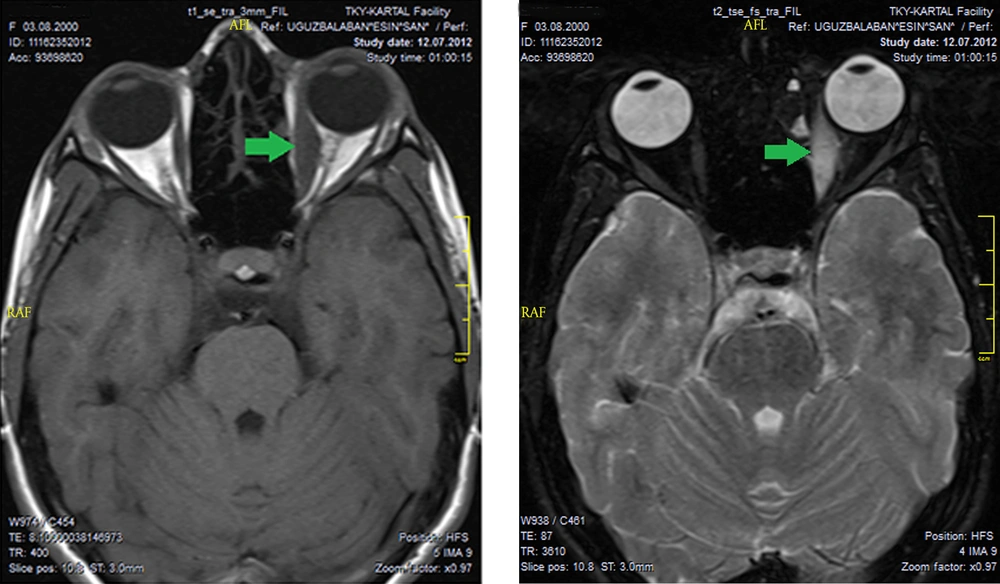

A 9-year-old girl presented to the pediatric clinic with a nonspecific headache, eye pain and restriction of left outward gaze and diplopia. Despite systemic antibiotic therapy following a preliminary diagnosis of afebrile cellulitis, the progression of complaints were noted and our clinic was consulted. Visual acuity was 20/20 in both eyes, biomicroscopic and fundus examination was normal. The exophthalmometry readings of the right and left eye were 15 mm and 18 mm, respectively. Left ocular eye movement was limited in outward gaze (Figure 1). Worth 4 dot test result was determined to be diplopia in far and near evaluation. Laboratory studies were normal. On the orbital MRI, taken SE T1-weighted images following gadopentetate dimeglumine (Gd-DTPA) on the axial and coronal plane, left medial rectus muscle was normal but increased signal intensity on T2W sequences was noted, and the presence of marked enhancement of contrast material following intravenous administration of contrast material (IVCM) (Figure 2). The imaging of the medial rectus muscle is typical of myositis and this typical image is used for differentiating NSOI from thyroid ophthalmopathy. The systemic steroid treatment (oral prednisone 1 mg/kg tapered slowly for one month) was initiated with a preliminary diagnosis of NSOI. Diplopia and ocular motility restriction were not present a week after control examination. MRI showed regression of the isolated myositis in the medial rectus. The definitive diagnosis of orbital subacute myosistis was established.

A, T1; B, T2